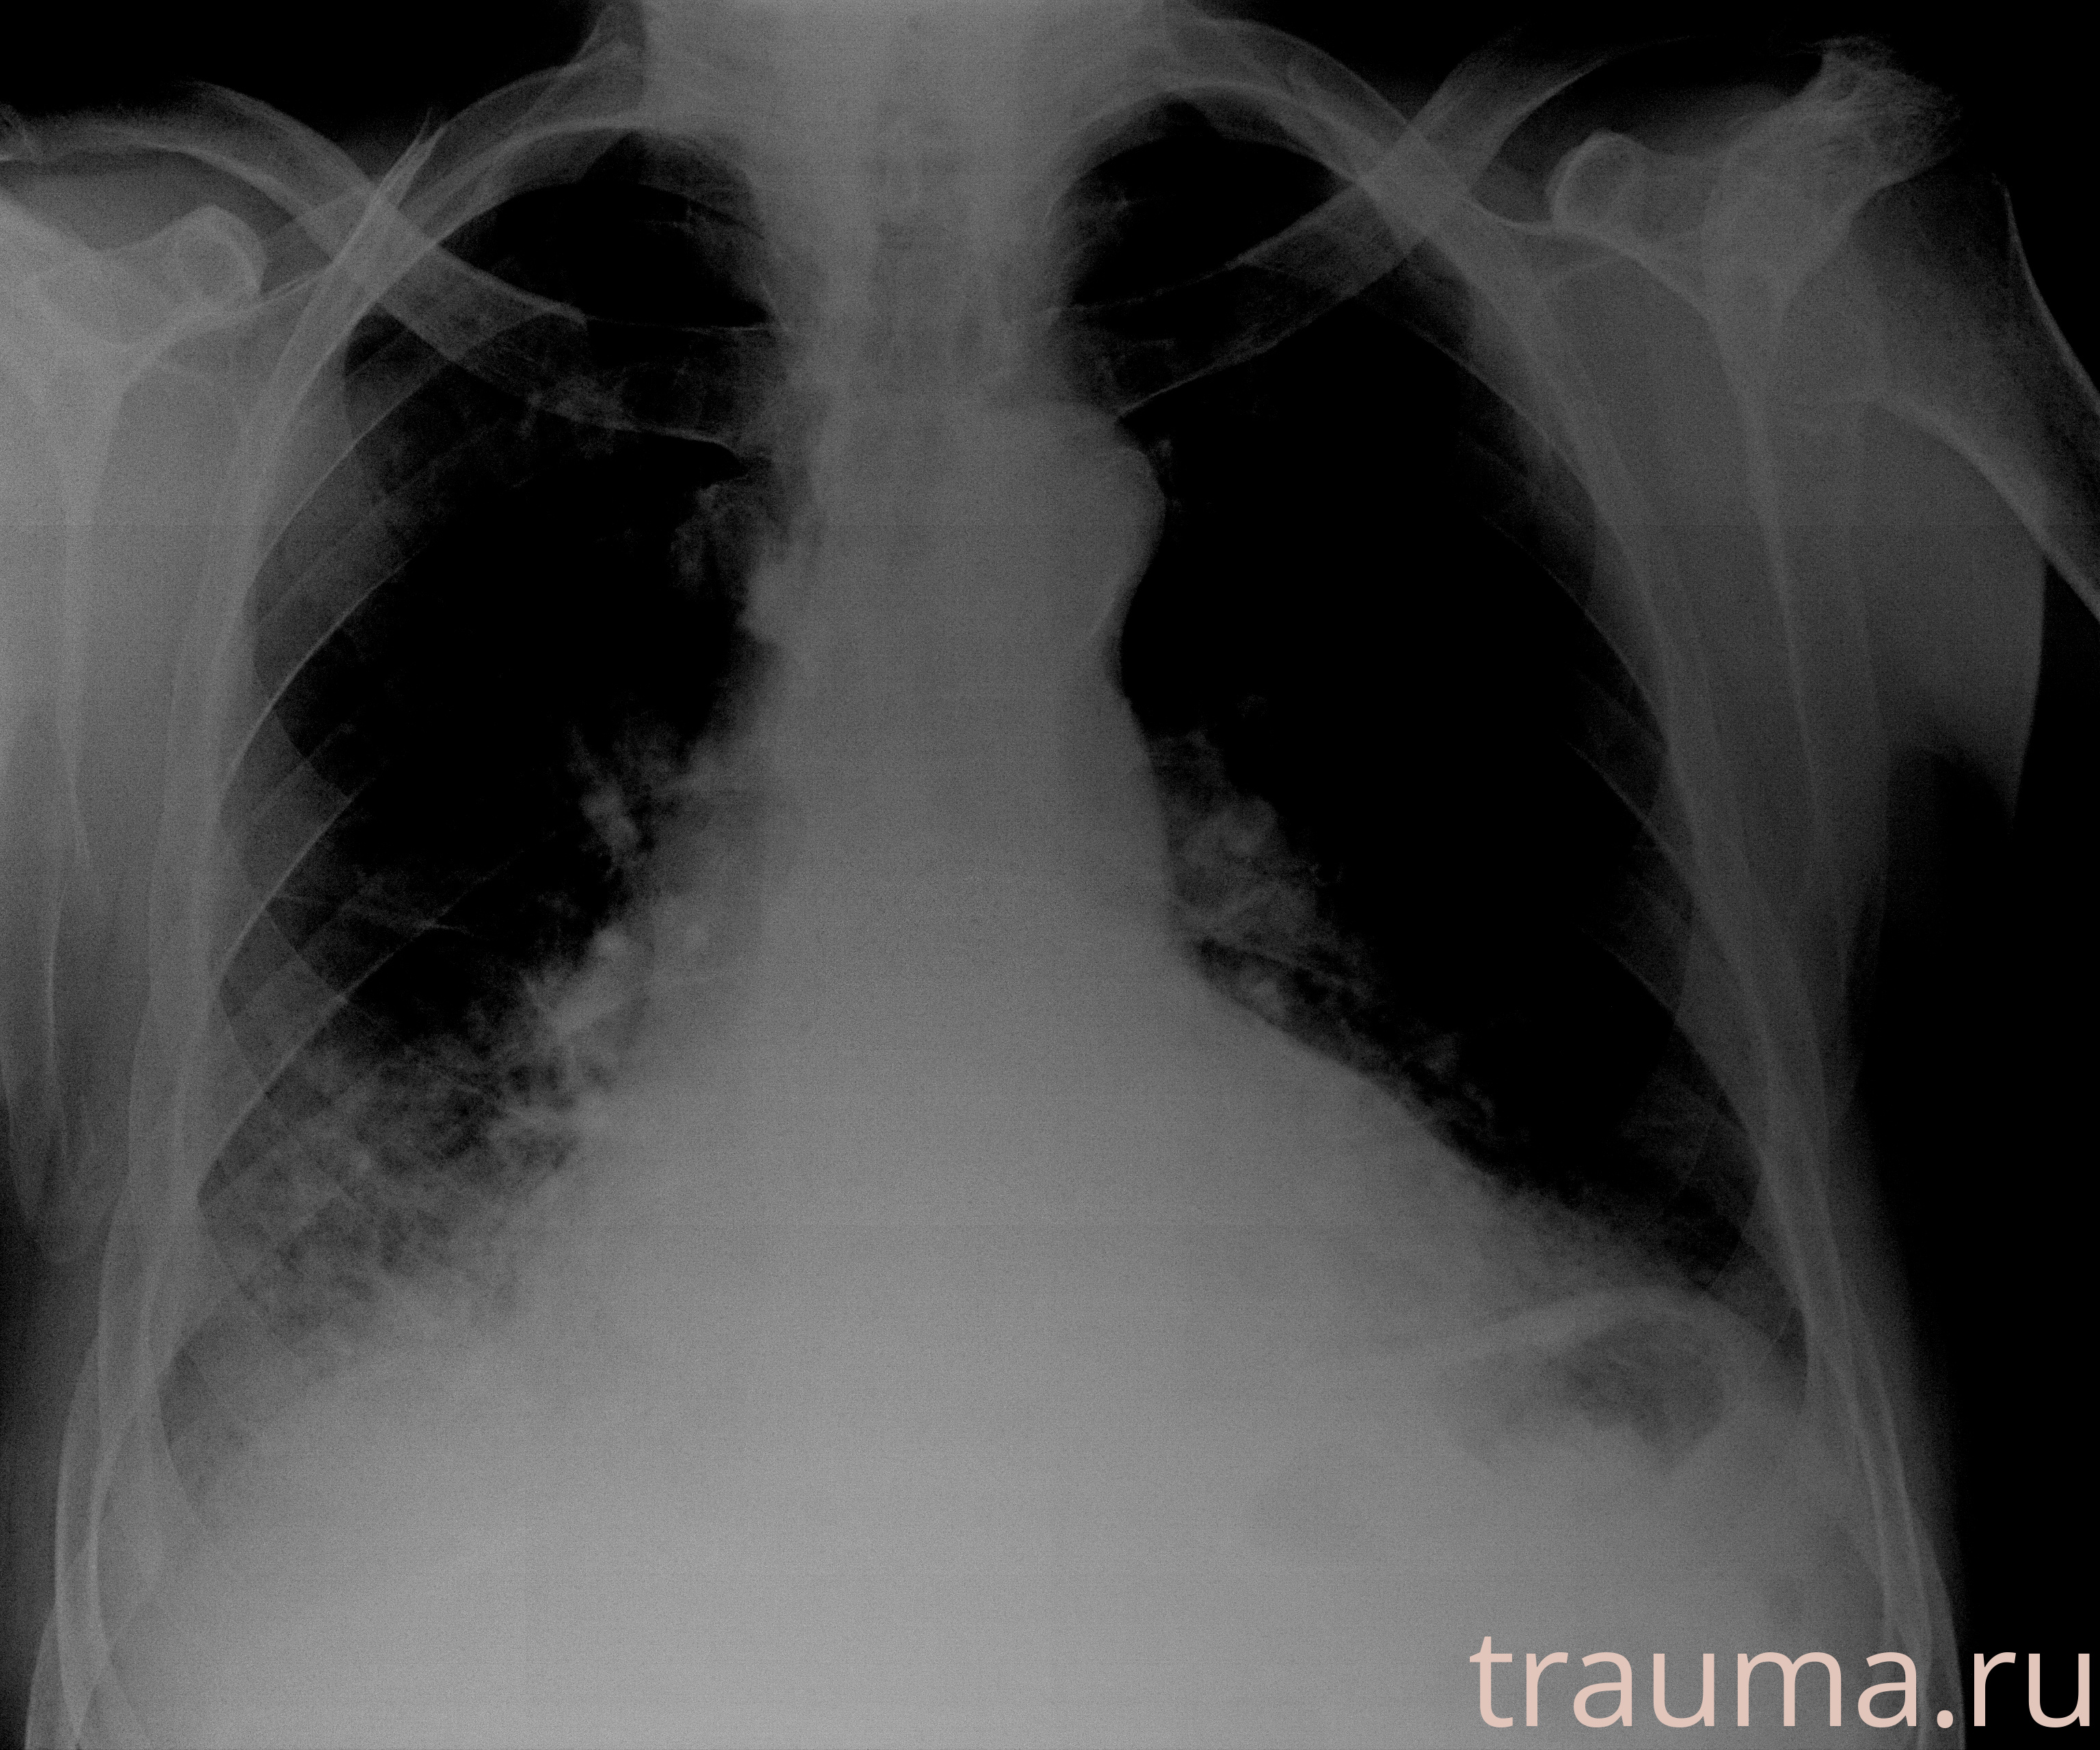

Рентгенограммы

Рентген на дому: по вашему адресу приезжает врач-рентгенолог, травматолог-ортопед с мобильным рентгеновским аппаратом, проводит диагностику травмы или заболевания, делает необходимые рентгенограммы, дает рекомендации по дальнейшему лечению. Получить качественные снимки в домашних условиях возможно благодаря уникальной методике, разработанной МосРентген Центром для института  Склифосовского